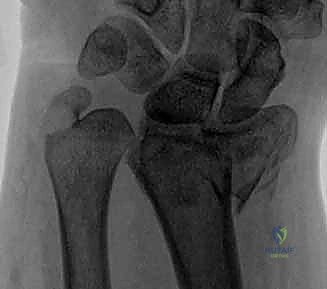

2. كسور رأس الزند (Ulnar Head Fractures)

رأس الزند هو الجزء المفصلي الدائري الذي يدور حوله الكعبرة.

* كسور مفصلية (Articular Fractures): تمتد خطوط الكسر لتشمل الغضروف المفصلي. إذا لم يتم إعادة العظام إلى وضعها التشريحي المثالي (Anatomic Reduction)، فإن المريض سيكون عرضة للإصابة بخشونة المفاصل المبكرة (Post-traumatic Osteoarthritis) وفقدان القدرة على تدوير الساعد.

* كسور غير مفصلية: تقع تحت السطح المفصلي مباشرة، ولكنها قد تؤدي إلى تشوه في زاوية رأس الزند.

صورة لكسر في رأس الزند